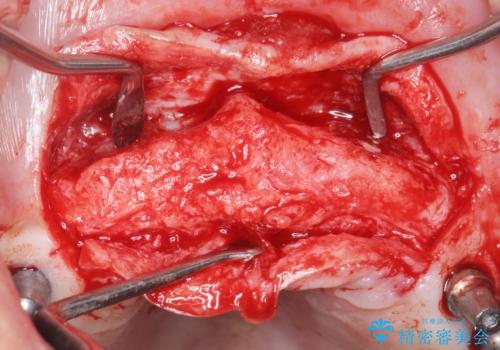

咬合関係がⅢ級(受け口)のため唇側に骨増生を行ったのちインプラント埋入(右上31左上3)を行いました。

治療途中で患者様が喫煙を再開され、最もタバコの影響を受けやすい上顎前歯部(右上31)インプラント周囲の骨吸収と少量の排膿を認めました。

長期的予後不良と判断した右上3フィクスチャーを除去し、人工骨による骨増生及び右上2に埋入を行いました。

保存可能な右上1のフィクスチャーは粘膜下にスリープさせ、左上2の埋入を行いました。